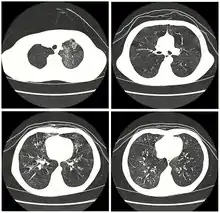

High resolution CT scan showing bronchiolitis obliterans with mosaic attenuation, bronchiectasis, air trapping and bronchial thickening[3]

Medical imaging

Early in the disease chest radiography is typically normal but may show hyperinflation.[6] As the disease progresses a reticular pattern with thickening of airway walls may be present.[4][6] HRCT can also show air trapping when the person being scanned breathes out completely; it can also show thickening in the airway and haziness in the lungs.[11] A common finding on HRCT is patchy areas of decreased lung density, signifying reduced vascular caliber and air trapping. This pattern is often described as a "mosaic pattern", and may indicate bronchiolitis obliterans.[6]